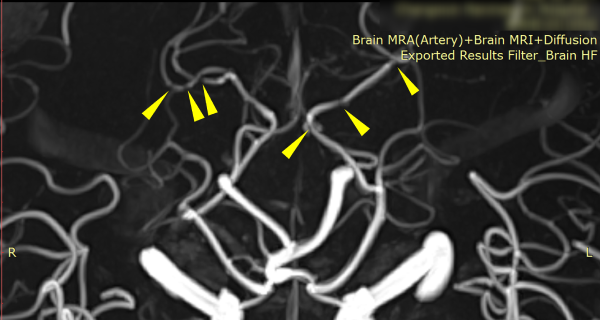

• 신경계(뇌출혈,뇌경색) 후유장해 보상전문

• 시리즈4 : MRI 검사 후 반드시 묻게 될 뇌혈관진단금 30가지 질문